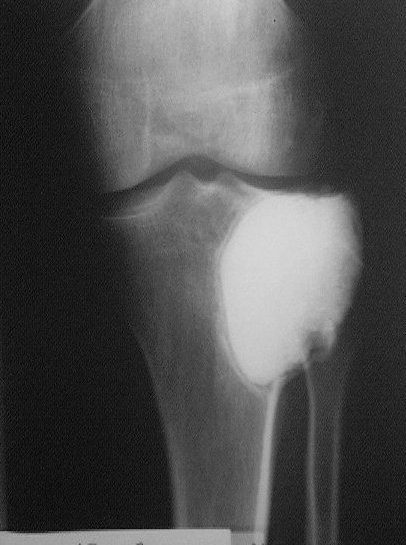

Около года назад больному 25 лет по поводу литической опухоли мыщелка б\б кости ( ОБК?)с выраженным болевым синдромом была произведенарасширенная открытая биопсия, экскохлеация опухоли.

В связи с неясностью диагноза до операции и отсутствия аллокости в тот момент интраоперационно было выполнено экспресс протезирование дефекта мыщелка акриловым цементом. Верхней стенкой дефекта была визуально неповрежденная суставная поверхность. Хрящевая пластина провисала - была выведена на уровень и "подперта" цементным спейсером. Больной осмотрен через год - ходит не хромая, сустав абсолютно спокойный, рентгенологически процедива опухоли нет. Хотелось бы услышать предложения по пластике дефекта - сроки, вид материала. Честно говорябоюсь трогать хрящ повторно.

Случай очень интересный! Увидеть бы снимки до операции. Можно обсудить состояние хряща "на цементе"-за счет чего он жив или там все-таки дефект? Щель сустава хорошая. Есть ли возможность проведения МРТ у больного?

Согласен с предыдущими мнениями. Данных за рецидив нет, функция приличная,пациент доволен. Зачем создавать лишние проблемы себе и больному?! Необходим только клинико-рентгенологический контроль в динамике. Кстати, метод замещения таких дефектов цементом используется часто за рубежом, результаты описаны в доступной англоязычной литературе, в частности - в Clin. Orth. и JBJS.

Субхондральное эндопротезирование костным цементом при доброкачественных опухолях давно используется в институте им. Вредена. Редко бывают рецидивы (костный цемент, полимеризуясь, нагревается до 70 градусов). Сроки наблюдений благополучного исхода более 20лет.